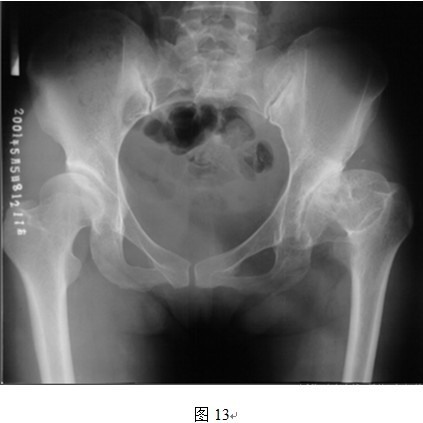

5. THRA不能有效延长肢体

图中所示左侧股骨颈短缩明显,进行THRA后因股骨颈长度不能延长,因此肢体长度不能得到恢复。